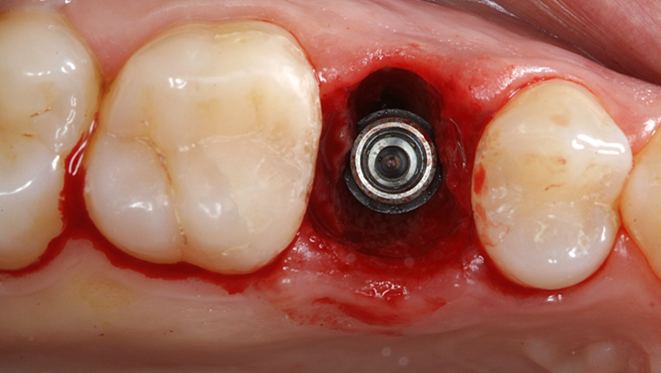

Clinical case: Extraction, immediate implant placement, & provisionalization

- Courtesy of Dr. Iulian Filipov, Romania -

Keywords

AnyRidge, R2GATE, guided surgery, immediate placement, immediate provisionalization, initial stability, Dr. Iulian Filipov, #25, maxillary posterior, immediate loading, Mega ISQ